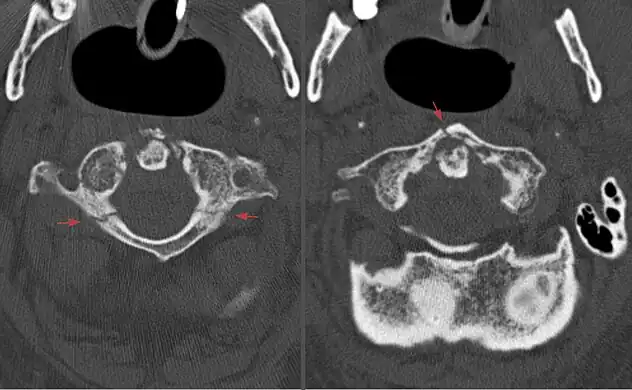

Axial CT scan showing a Jefferson fracture.